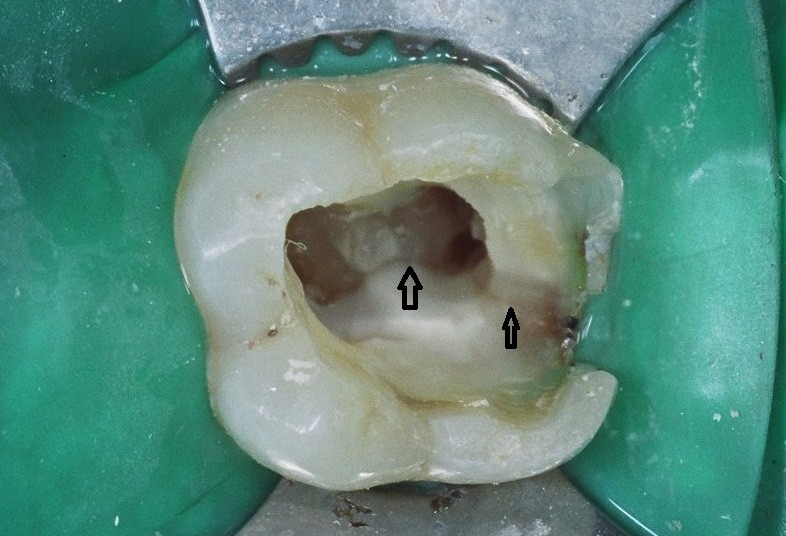

A toothache caused by a broken tooth (tooth fracture) without associated cavity or advanced gum disease. Biting on the area of tooth fracture can cause severe sharp pains. These fractures are usually due to chewing or biting hard objects such as hard candies, pencils, nuts, etc. Sometimes, the fracture can be seen by painting a special dye on the cracked tooth. Treatment usually is to protect the tooth with a crown. However, if placing a crown does not relieve pain symptoms, a root canal procedure may be necessary.